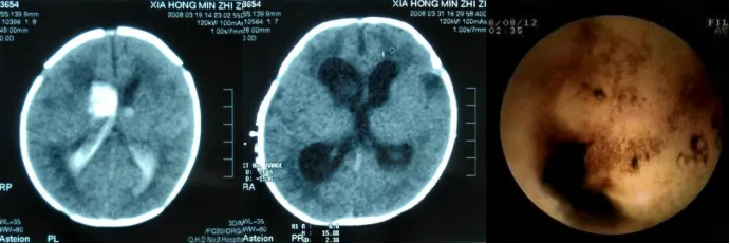

头颅CT检查是颅内血肿有效、迅速的确诊方法。临床上通常根据头颅CT检查所见,动态跟踪颅内血肿的变化情况。发病初期,新鲜血肿表现为均匀一致的高密度(CT片上呈白色),随着血肿内血红蛋白分解,其密度逐渐降低(CT片上病灶的颜色逐渐由白色向黑色转变),直径不超过2cm的血肿一般在3周或更早就变成等密度,而大的血肿常需4-6周才能演变为等密度。但CT所见的血肿缩小,只是根据高密度逐渐变为等密度来判断,而实际上此时血凝块大小变化不大,并没有真正地吸收。

近年来,随着神经内镜技术的日益成熟,内镜下脑室探查所见使得人们对颅内血肿的吸收状况有了新的认识。经神经内镜技术探查发现脑室内仍有大量陈旧血斑,说明至少经过5个月血肿仍没有完全吸收。这些血肿的破坏产物对脑组织会持续产生一系列继发性损害。由此可见,颅内出血后尽早清除血肿,减轻继发性脑损害,有助于远期神经功能的恢复。